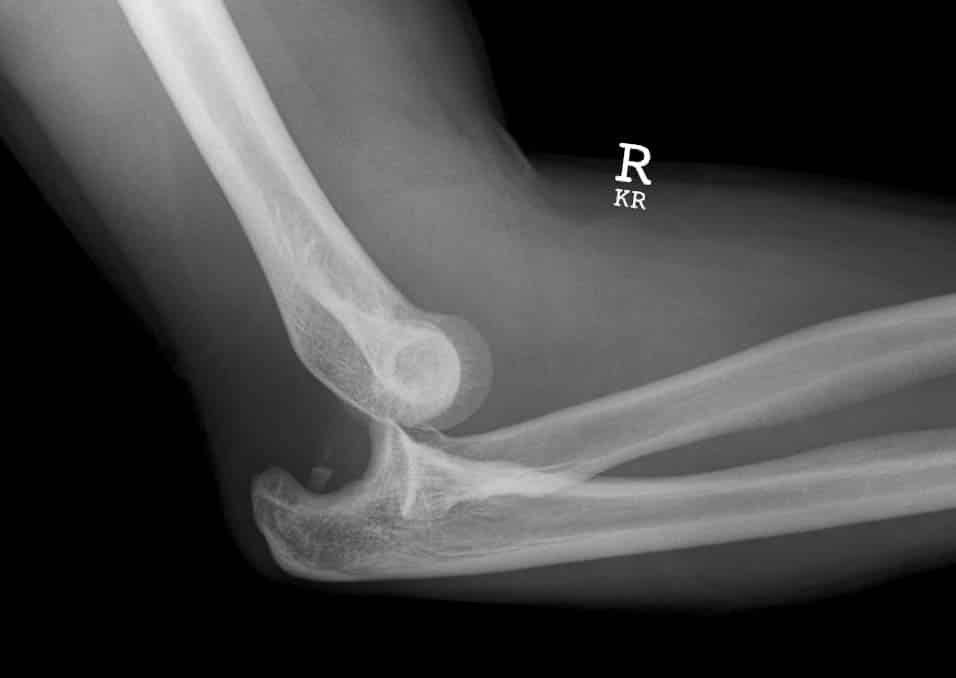

The elbow is the joint connecting the upper arm to the forearm. It is classed as a hinge-type synovial joint. In this article, we shall look at the anatomy of the elbow joint – its articulating surfaces, movements, stability, and the clinical relevance. Pro Feature - 3D Model You've Discovered a Pro Feature Access our 3D Model Library Explore, cut, dissect, annotate and manipulate our 3D models to visualise anatomy in a dynamic, interactive way. Learn More Structures of the Elbow Joint Articulating Surfaces The elbow joint consists of two separate articulations: Trochlear notch of the ulna and the trochlea of the humerus Head of the radius and the capitulum of the humerus Note: The proximal radioulnar joint is found within same joint capsule of the elbow, but most resources consider it as a separate articulation. By TeachMeSeries Ltd (2025) Fig 1Anterior and posterior views of the articulations of the elbow joint Joint Capsule and Bursae Like all synovial joints, the elbow joint has a capsule enclosing the joint. This is strong and fibrous, strengthening the joint. The joint capsule is thickened medially and laterally to form collateral ligaments, which stabilise the flexing and extending motion of the arm. A bursa is a sac-like structure containing a small amount of synovial fluid. It functions to decrease friction between tendons, bone, and skin during movement. There are many bursae in the elbow, but only a few have clinical importance: Intratendinous olecranon – located within the tendon of the triceps brachii. Subtendinous olecranon – between the olecranon and the tendon of the triceps brachii, reducing friction between the two structures during extension and flexion of the arm. Subcutaneous olecranon bursa – between the olecranon and the overlying connective tissue (implicated in olecranon bursitis). Ligaments The joint capsule of the elbow is strengthened by ligaments medially and laterally. The radial collateral ligament is found on the lateral side of the joint, extending from the lateral epicondyle, and blending with the annular ligament of the radius (a ligament from the proximal radioulnar joint). The ulnar collateral ligament originates from the medial epicondyle, and attaches to the coronoid process and olecranon of the ulna. By TeachMeSeries Ltd (2025) Fig 2Ligaments of the elbow joint. Blood Supply The elbow joint receives a rich arterial supply from a surrounding network of vessels, which is formed by branches of the brachial artery. Innervation The elbow joint is innervated by branches of the medial, musculocutaneous, radial and ulnar nerves. Movements The orientation of the bones forming the elbow joint produces a hinge type synovial joint, which allows for extension and flexion of the forearm: Extension – triceps brachii and anconeus Flexion – brachialis, biceps brachii, brachioradialis Note – pronation and supination do not occur at the elbow – they are produced at the nearby radioulnar joints. Clinical Relevance Injuries to the Elbow Joint Bursitis Subcutaneous bursitis: Repeated friction and pressure on the bursa can cause it to become inflamed. Because this bursa lies relatively superficially, it can also become infected (e.g. skin laceration from a fall on the elbow) Subtendinous bursitis: This is caused by repeated flexion and extension of the forearm, commonly seen in assembly line workers. Usually flexion is more painful as more pressure is put on the bursa. Dislocation An elbow dislocation usually occurs when a young child falls on a hand with the elbow flexed. The distal end of the humerus is driven through the weakest part of the joint capsule, which is the anterior side. The ulnar collateral ligament is usually torn and there can also be ulnar nerve involvement Most elbow dislocations are posterior, and it is important to note that elbow dislocations are named by the position of the ulna and radius, not the humerus. By Life in the Fast Lane [CC BY-SA 4.0] Fig 3X-ray of a posterior dislocation of the elbow. Epicondylitis (Tennis elbow or Golfer’s elbow) Most of the flexor and extensor muscles in the forearm have a common tendinous origin. The flexor muscles originate from the medial epicondyle, and the extensor muscles from the lateral. Sportspersons can develop an overuse strain of the common tendon – which results in pain and inflammation around the area of the affected epicondyle. Typically, tennis players experience pain in the lateral epicondyle from the common extensor origin. Golfers experience pain in the medial epicondyle from the common flexor origin. This is easily remembered as golfers aim for the ‘middle’ of the fairway, while tennis players aim for the ‘lateral’ line of the court! Supracondylar Fracture A supracondylar fracture usually occurs due to a fall onto on outstretched, extended hand in a child (95%) but more rarely can occur by a direct impact onto a flexed elbow. It is typically a transverse fracture, spanning between the two epicondyles in the relatively weak epicondylar region formed by the olecranon fossa and coronoid fossa which lie opposite each other in the distal humerus. Direct damage, or swelling can cause the interference to the blood supply of the forearm via the brachial artery. The resulting ischaemia can cause Volkmann’s ischaemic contracture – uncontrolled flexion of the hand, as flexors muscles become fibrotic and short. There also can be damage to the medial, ulnar or radial nerves. As a result, the neurovascular examination and documentation of all patients presenting with these injuries is vital. Sometimes, the blood supply can be interrupted acutely leading to a ‘pale, pulseless’ limb often in a child, usually requiring emergency surgery. Do you think you’re ready? Take the quiz below Pro Feature - Quiz The Elbow Joint Question 1 of 3 Submitting... Skip Next Rate question: You scored 0% Skipped: 0/3 1800 More Questions Available Upgrade to TeachMeAnatomy Pro Challenge yourself with over 1800 multiple-choice questions to reinforce learning Learn More Rate This Article